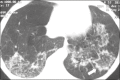

Figure 1

HIV-positive patient with pneumocystosis. High-resolution computed tomography of the upper lung lobes, showing diffuse ground-glass opacities in the pulmonary parenchyma and sparse small foci of consolidation.